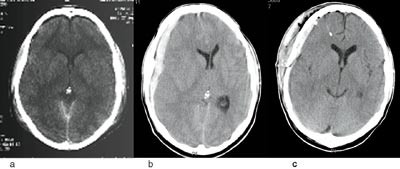

Ved ankomst til Christchurch Hospital 36 timer etter skaden hadde tilstanden bedret seg noe. Pasienten kunne vekkes, men var urolig og desorientert, med GCS-skåre 12. Pupillene var symmetriske, og det ble ikke funnet fokalnevrologiske utfall. Bilateralt Battles’ tegn gav sterk mistanke om brudd i skallebasis. Han måtte sederes og intuberes før det var mulig å gjøre CT, som viste nedsatt tetthet over begge frontallapper forenlig med væskeansamling i subaraknoidalrommet (fig 3a). Det var ingen tegn til annen intrakranial skade eller skallebrudd.

Pasientens mor kom på besøk, og 2. mars gikk han en kort tur ut sammen med henne. Han skled på glattisen utenfor sykehuset, falt og slo seg i hodet en gang til. Ambulanse ble tilkalt og han ble kjørt til Akuttmottaket. Ved undersøkelsen var han bevisstløs, med GCS-skåre 6. Høyre pupill var utvidet og uten lysreaksjon. CT viste et stort akutt subduralt hematom på høyre side (fig 3b og c). Pasienten ble umiddelbart operert med kraniotomi og evakuering av hematomet. Han ble raskt bedre, slik at tilstanden etter tre dager var uendret sammenliknet med før den siste hodeskaden, bortsett fra temporal hemianopsi på venstre side.